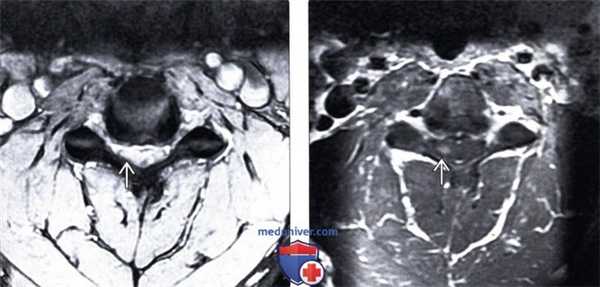

(Слева) На аксиальном T2*GRE МР-И видны признаки умеренно выраженного фораминального стеноза на фоне относительно легких дегенеративных изменений дугоотростчатых суставов и гипертрофии унковертебральных суставов. Спинной мозг с признаками усиления сигнала вследствие хронического сдавления и миеломаляции.

(Справа) Т1-ВИ с КУ: признаки фораминального стеноза вследствие гипертрофии унковертебральных суставов и дегенеративных изменений дугоотростчатых суставов, в толще спинного мозга виден очаг усиления сигнала, представляющий собой зону миеломаляции.

(Слева) На аксиальной МРТ (T2*GRE) определяется умеренный фораминальный стеноз, обусловленный легкими детенеративными изменениями дугоотростчатых суставов и гипертрофией унковертебральных суставов. Гиперинтенсивный сигнал в спинном мозге обусловлен его хроническим сдавлением и миеломаляцией.

(Справа) На аксиальной MPT (Т1ВИ C+) определяется фораминальный стеноз на фоне гипертрофии унковертебральных суставов, дегенеративных изменений дугоотростчатых суставов и миеломаляции с накоплением контраста в спинном мозге.